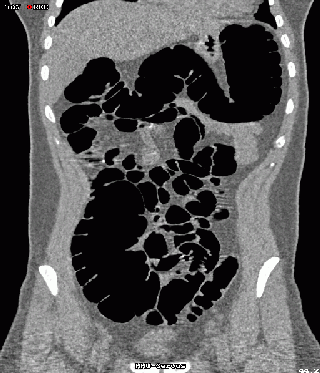

Links sind die Originaldaten, rechts die entrauschten Daten abgebildet.

Der mit Luft gefüllte Darminnenraum erscheint schwarz. Bei anderer Kontrasteinstellung wird jedoch deutlich, dass auch im Darminnenraum das Rauschen so stark sein kann, dass Luft und dünne Darmfalten stellenweise nicht anhand der Helligkeitswerte unterschieden werden können. Nach dem Entrauschen ist dies dann möglich.